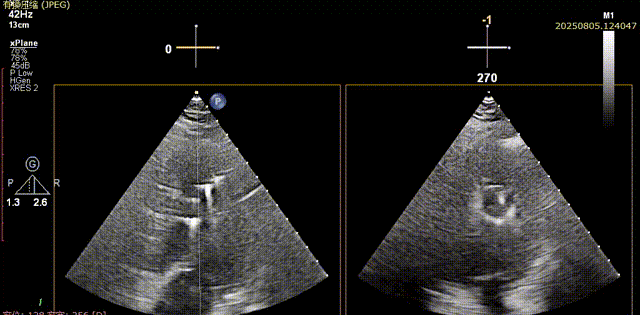

术前胸骨旁长轴切面可见流出道结构良好,五腔心切面可见主动脉瓣少中量反流

流出道结构观察

五腔心切面观察